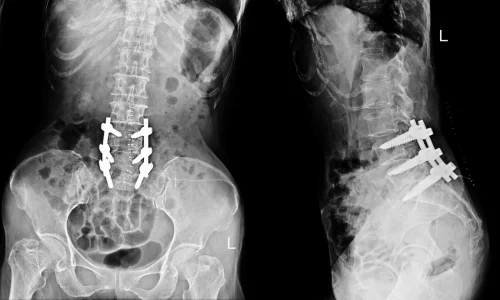

Removes part of the vertebra (lamina) to relieve nerve pressure, easing back and leg pain caused by spinal stenosis or disc issues, and improving mobility.